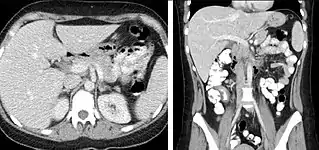

The most common technique is to perform portal venous phase imaging in the abdomen and pelvis (approximately 60–90 seconds after contrast administration, figure 2). This results in near optimal contrast opacification of the majority of the solid abdominal organs and it is used for a wide variety of indications: nonspecific abdominal pain; hernia; infection; masses (with a few exceptions such as hypervascular, renal, and some hepatic tumors); and in most follow-up examinations. As a general rule, this single phase is adequate unless there is a specific clinical indication that has been shown to benefit from other phases.

FIGURE 2. Contrast enhanced CT demonstrating parenchymal enhancement of the intra-abdominal organs in the portal venous phase (axial left, coronal reformat right).